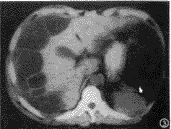

囊性淋巴管瘤:为均匀水样密度的多房或单房薄壁囊性肿块,大小4cm×3cm×8cm~8cm×7cm×10cm(图2),增强后,囊壁轻度均匀强化,大部分形态规整,界清,周围组织轻度受压移位,但其中有1例肠系膜上巨大囊性无分房、均匀水样密度、无壁的囊性淋巴管瘤术前CT误诊为腹水。

图2 囊性淋巴管瘤,为薄壁囊性包块,其内均匀水样密度